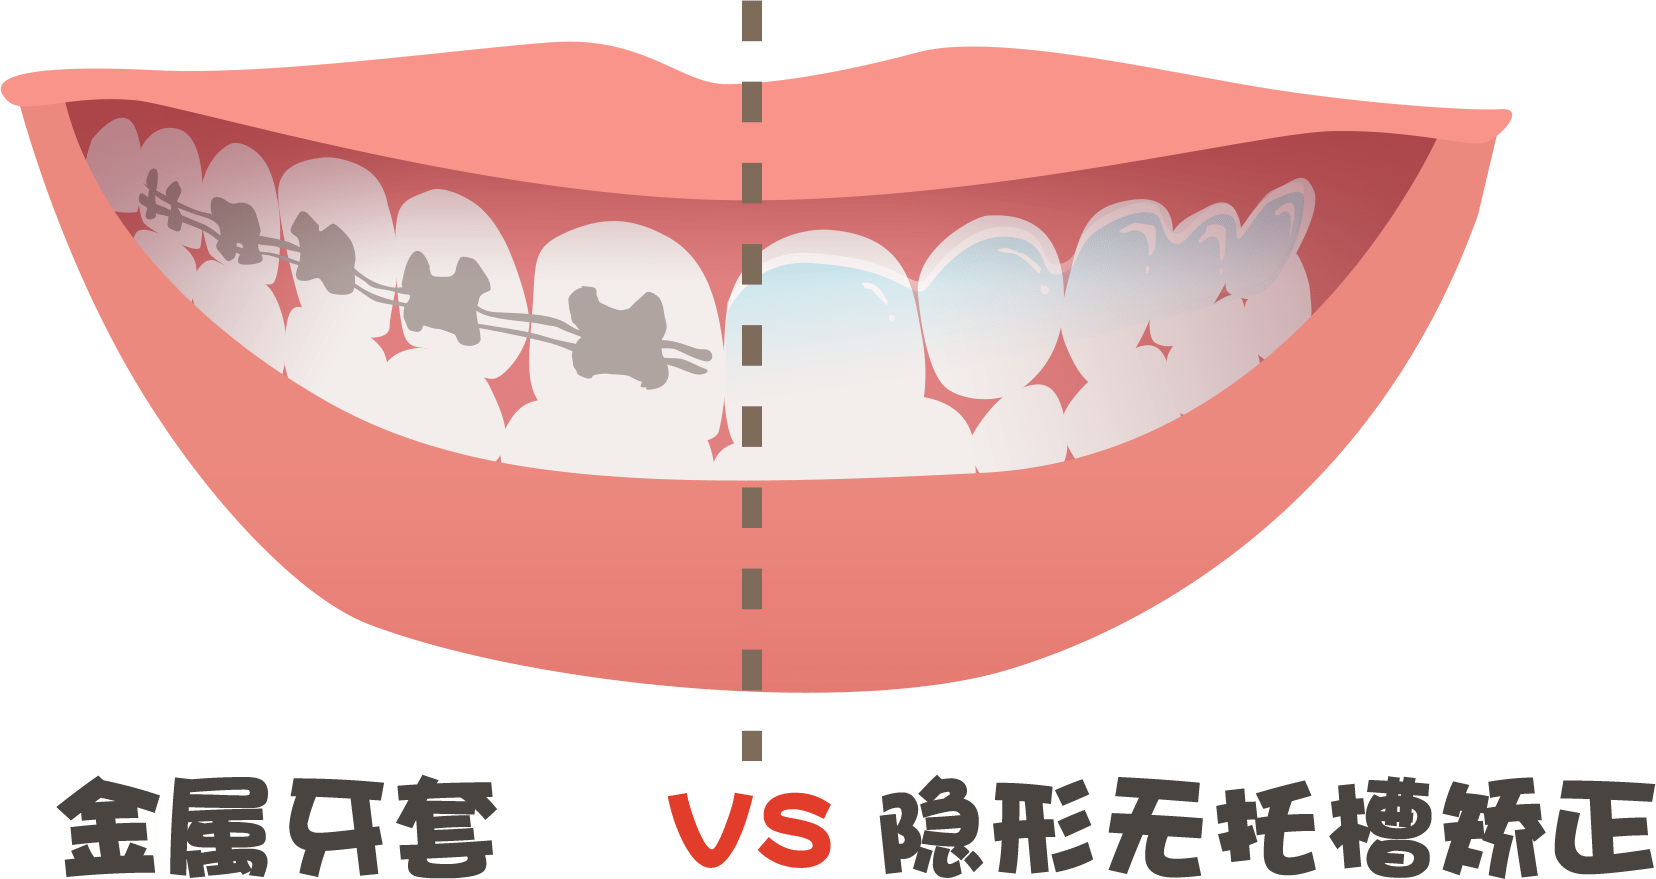

隐形矫正的价格往往高于传统矫正,但是舒适度和美观性会更胜一筹;

对于某些难度特别大的矫正,医生多会偏向于传统的固定矫正,因为技术更成熟,更容易驾驭。